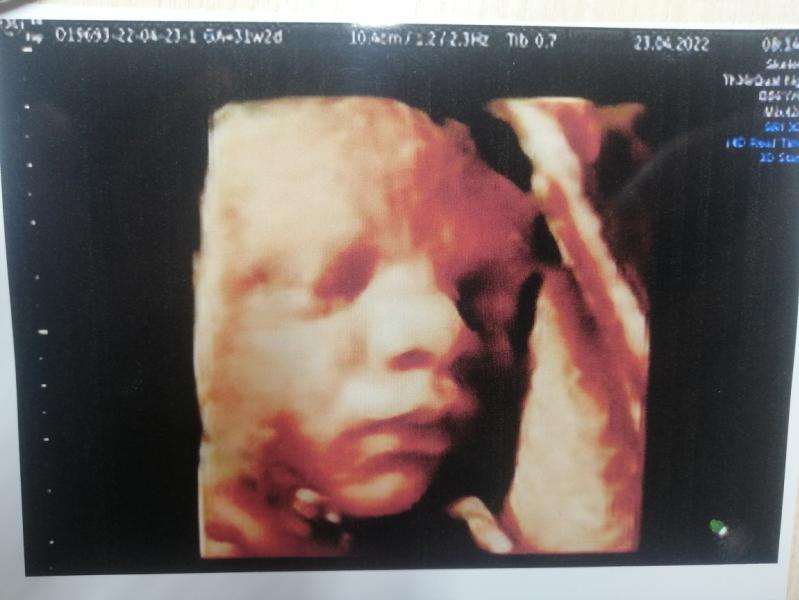

Сходили на 3 скрининг. Слава Богу всё хорошо🙏. Пупсик мой уже перевернулся вниз головой 😇 Вач сказала, вылетый папа😃 ещё и богатырь 2150. Развитие на 33 недели в наши неполные 32. Теперь можно спокойно жить дальше в ожидании часа "Х" 🥰